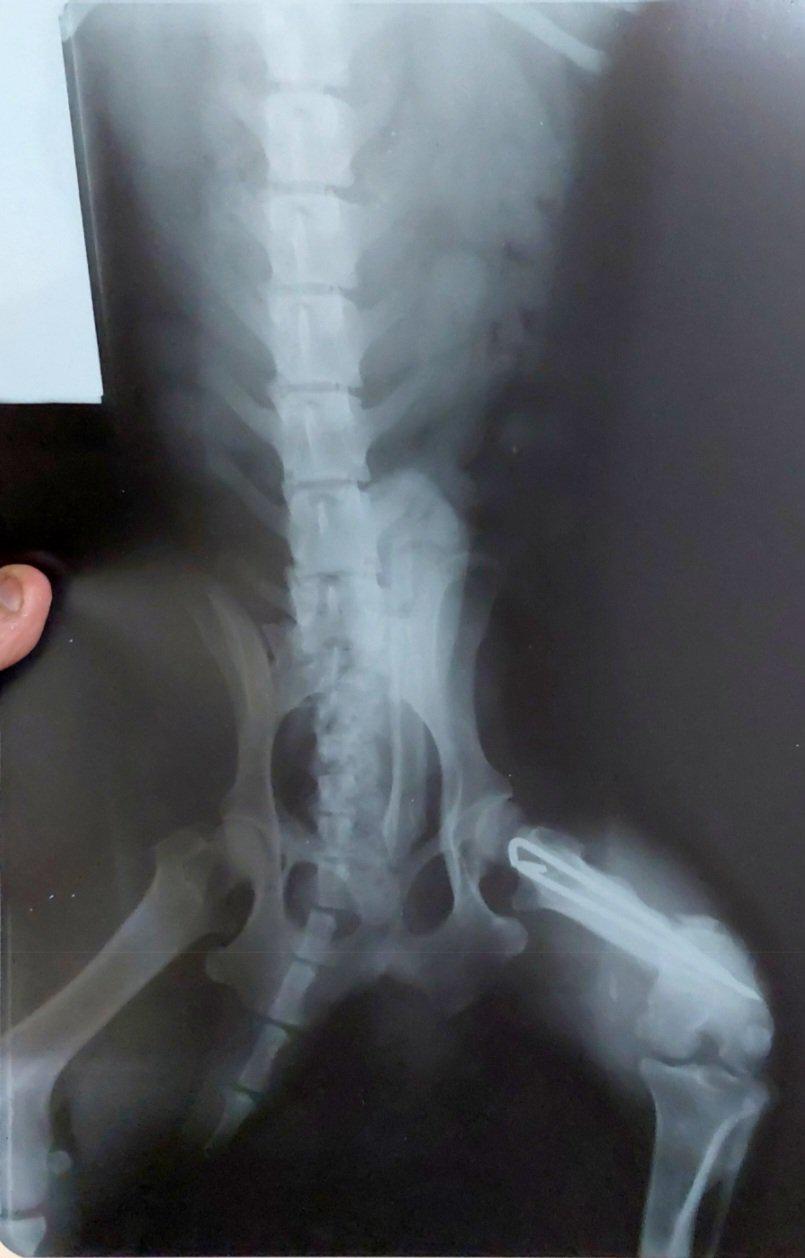

FOTO: la radiografía de un perro que se usó como certificado para obtener una pensión por invalidez. Diagnóstico: trastorno de disco lumbar e hipertensión. Ocurrió en Corrientes en 2022

El Gobierno denunció un esquema de corrupción en la Agencia Nacional de Discapacidad (ANDIS) por 3.400 millones de dólares, a través de la facturación de prestaciones médicas falsas. La denuncia, realizada por Diego Spagnuolo y investigada por el fiscal Guillermo Marijuan, revela que solo el 7% de las pensiones por invalidez laboral cumplen con los requisitos. Se encontraron radiografías falsas, documentos médicos con poemas y pruebas inverosímiles. El 30-50% de las pensiones otorgadas durante gobiernos kirchneristas podrían ser dadas de baja tras una auditoría exhaustiva. Además, se descubrieron gastos irregulares en la contratación de artistas y agasajos.